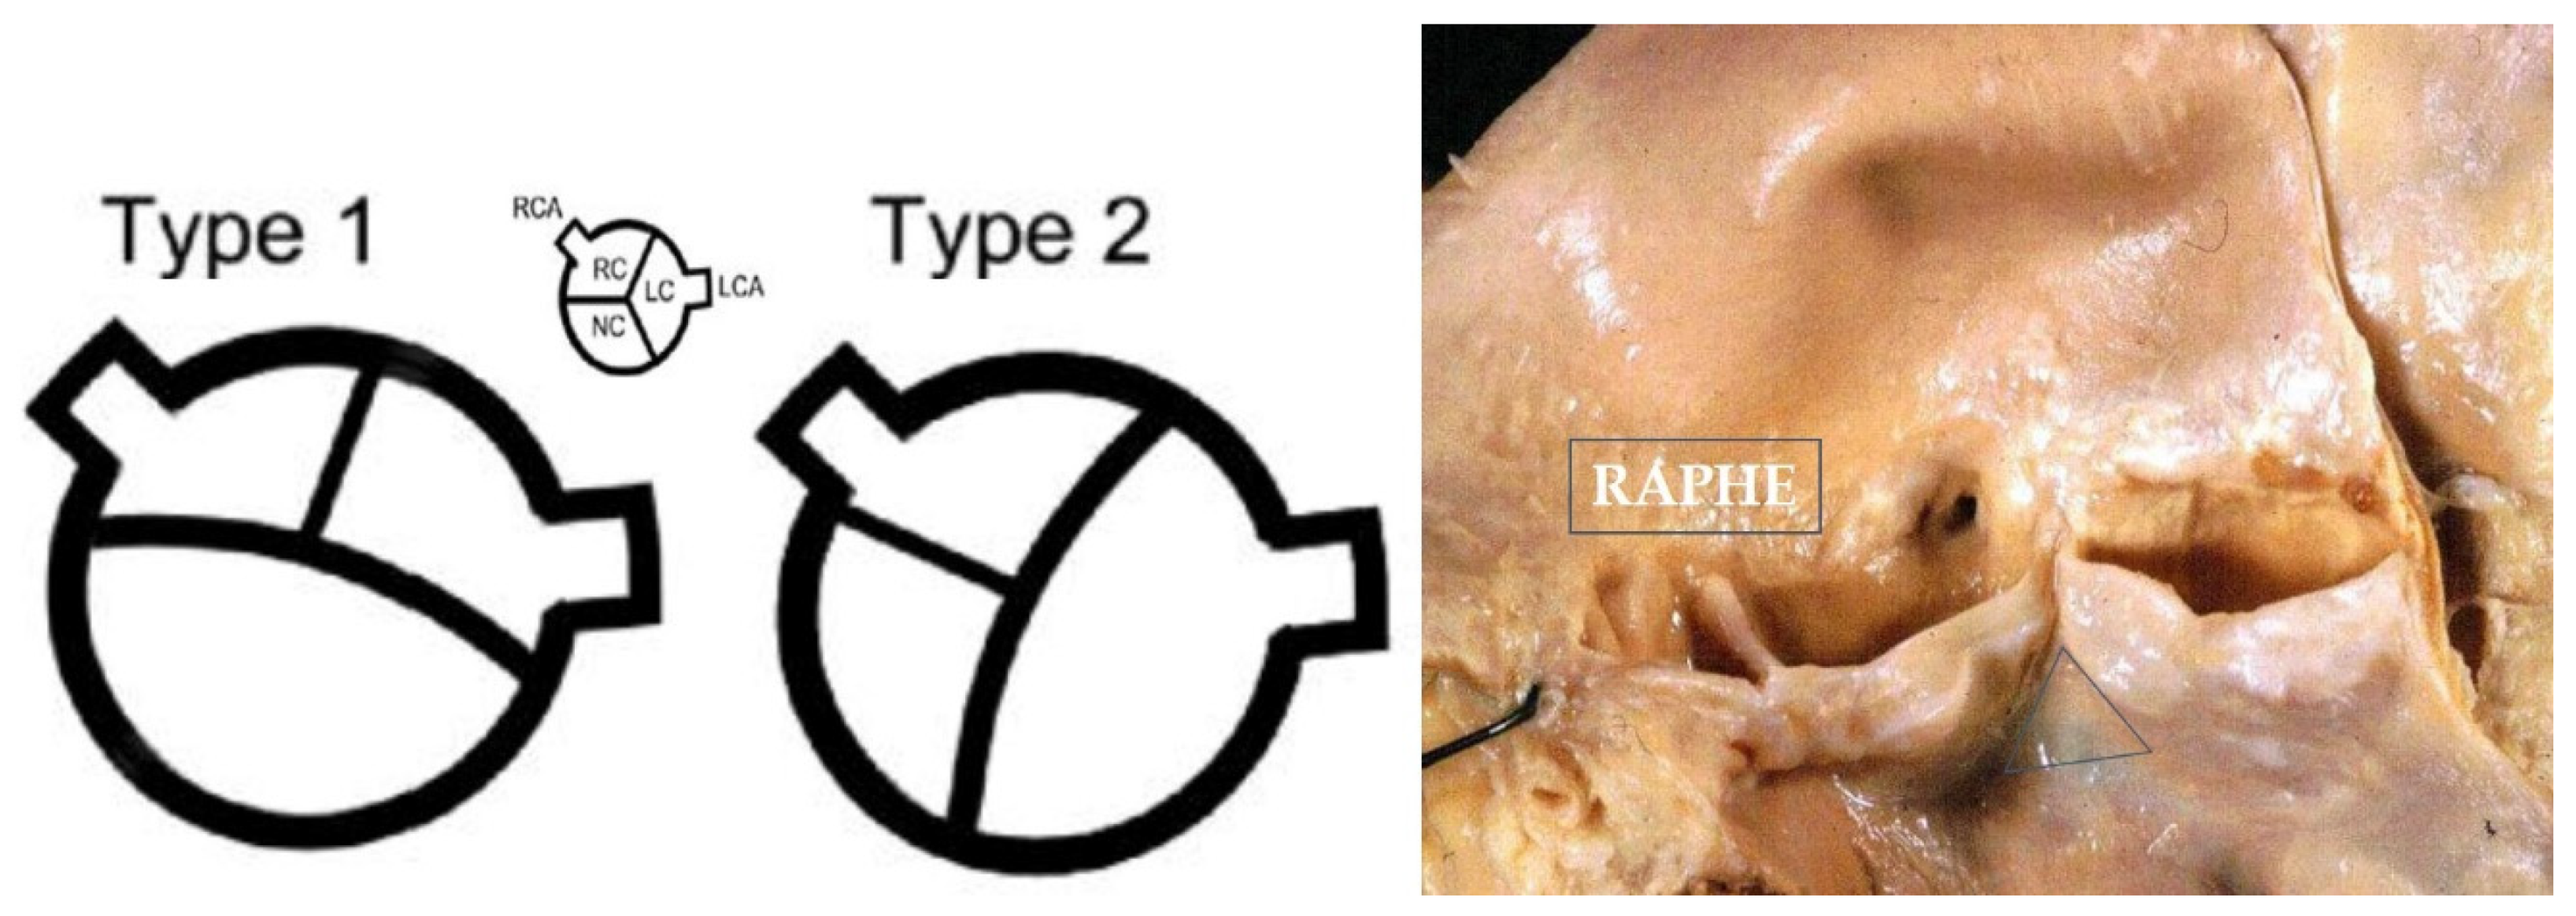

3.1. Congenital Malformations